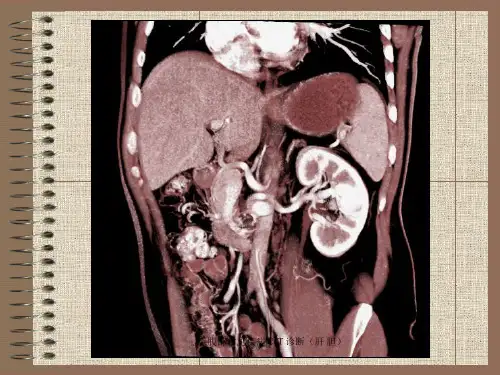

体位固定从膈顶向下扫描至肾脏下缘,是上腹部CT 扫描的基本范围。

图像重建图像解读根据重建得到的图像,观察肝、胆、胰、脾等器官有无异常病变。

图像解读与报告02常见疾病影像表现1肝脏疾病23CT表现为肝脏体积缩小,边缘不规则,肝实质内出现不规则低密度区,肝门部胆管扩张。

肝硬化CT表现为肝实质内不均匀低密度区,边缘呈分叶状,有时中心区可见钙化。

肝癌CT表现为肝脏密度降低,肝脏边缘圆钝,肝内血管纹理不清。

脂肪肝03胆囊炎CT表现为胆囊壁增厚,胆囊周围可见炎症细胞浸润。

肾脏疾病肾结石01CT表现为肾盂内不均匀高密度影,边缘不规则,有时可见点状钙化。

肾癌02CT表现为肾实质内不均匀低密度区,边缘呈分叶状,有时中心区可见钙化。

肾结核03CT表现为肾实质内多发低密度区,边缘模糊,肾盂肾盏变形。